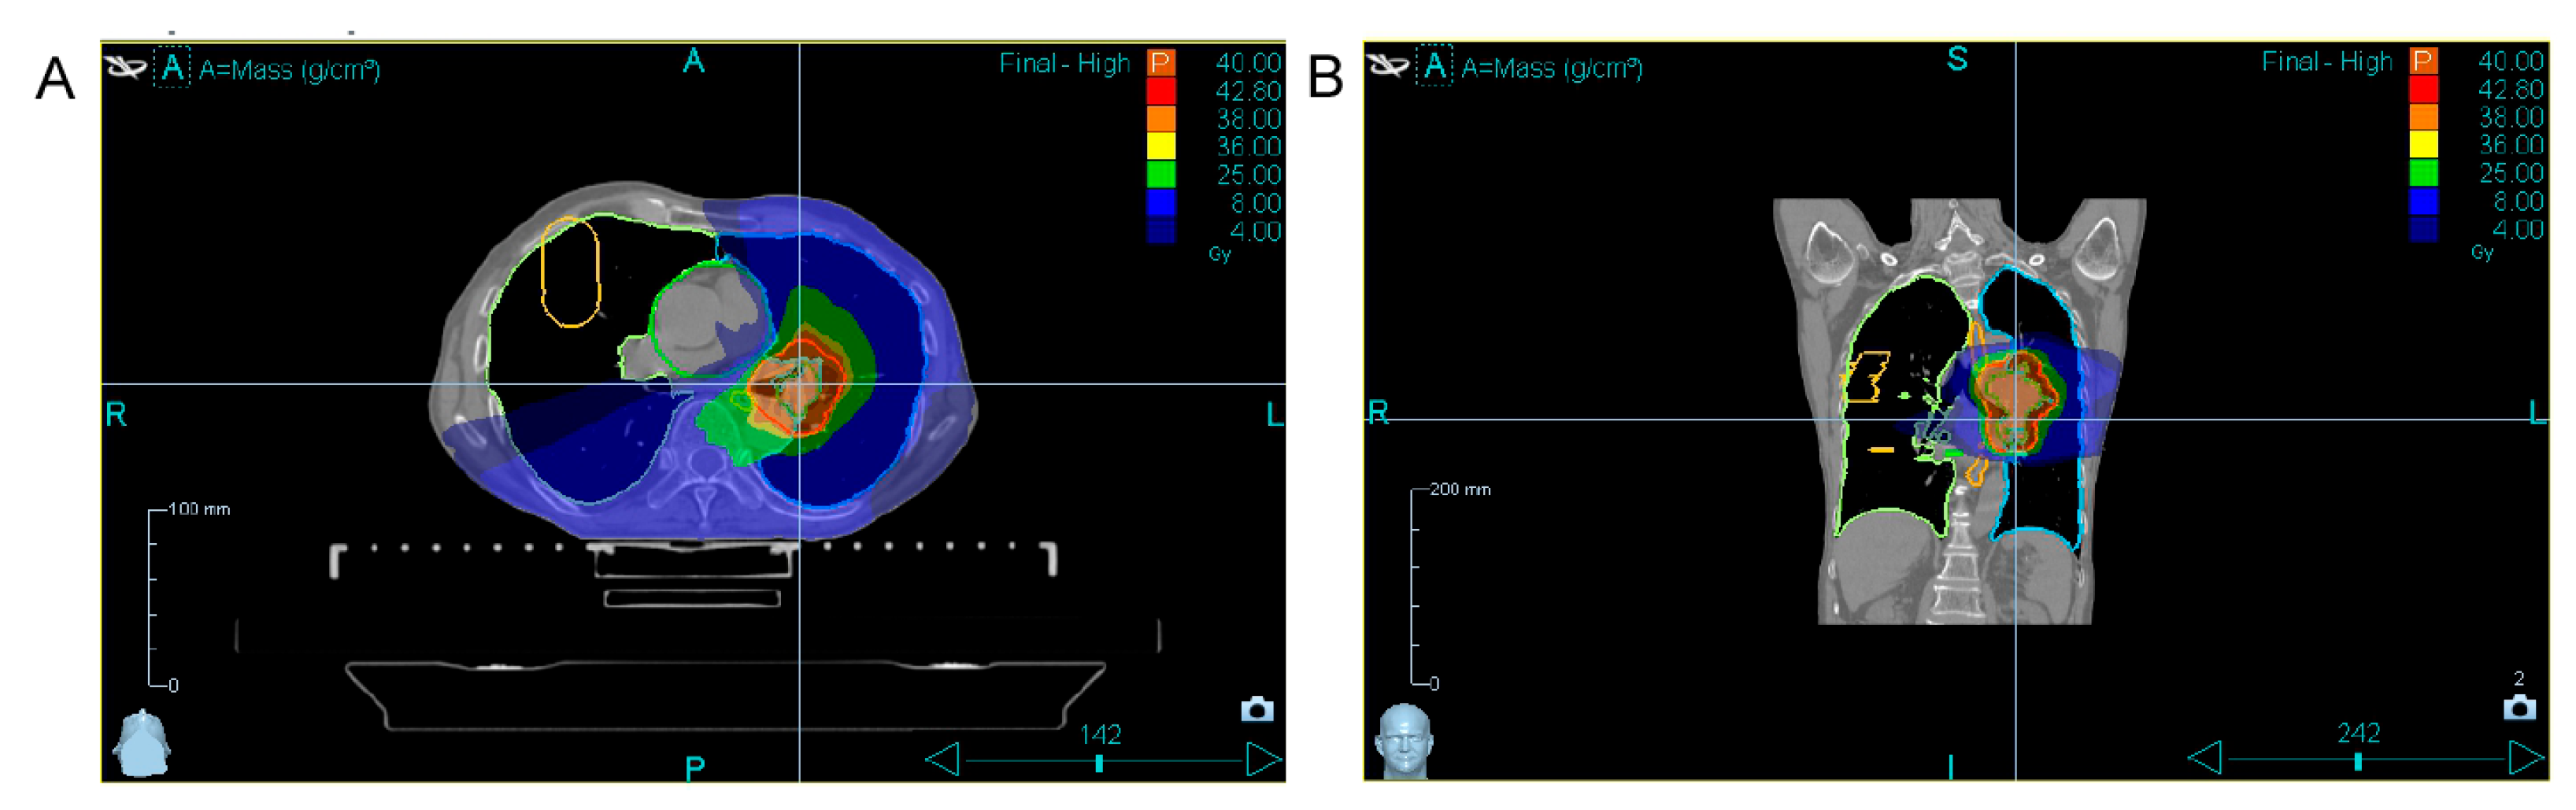

| 24 October– 4 November 2024 | Combined tomotherapy + immunotherapy treatment. Tomotherapy: ROD-5Gy, SOD-40Gy (8 fractions, 1 fraction per day except weekends). Immune cell therapy: 24 October—first infusion of autologous activated T lymphocytes. 31 October—second infusion of autologous activated T lymphocytes. |

| 19 December 2024 | Chest CT scan shows positive dynamics; the tumor decreased in size. CTC measurement (after combined treatment). |